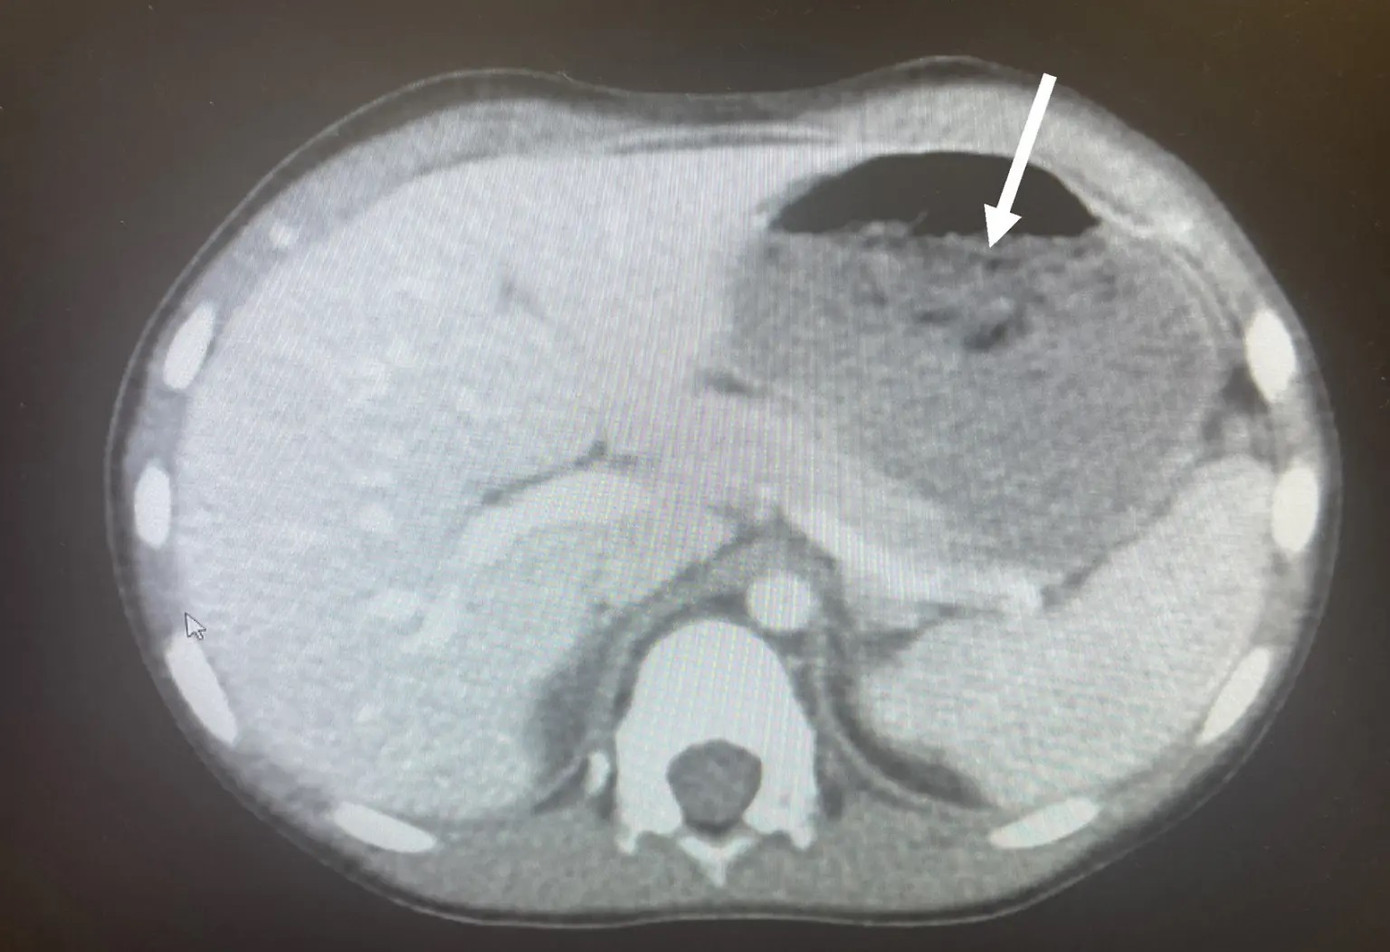

Nhóm chăm sóc sức khỏe, do Tiến sĩ Chizite Iheonunekwu của Phòng khám Cleveland đứng đầu, đã phát hiện ra chiếc bụng căng phồng của cậu bé khi chụp cắt lớp.